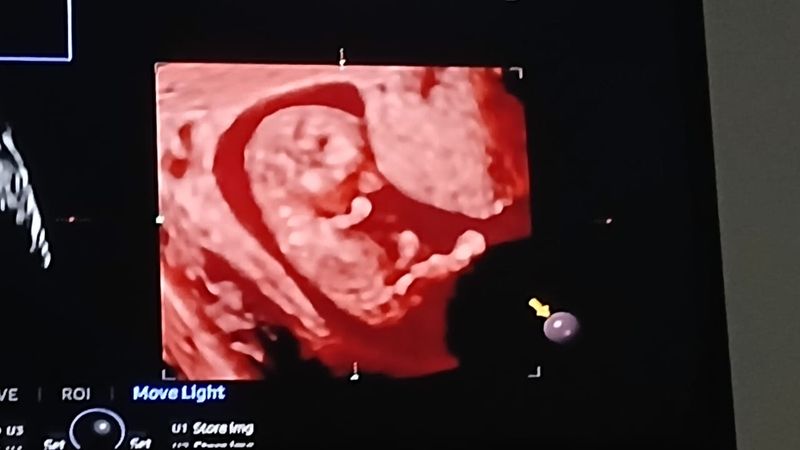

Minhas primeiras fotinhas

Eu ainda estou no forminho, mas a mamãe já tem várias fotos e vídeos, confere aí em baixo meu pessoal! 👶